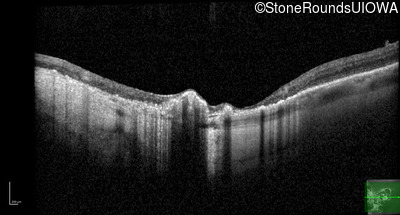

Optical Coherence Tomography - Left - 10/140

Exemplar / OCT Stack